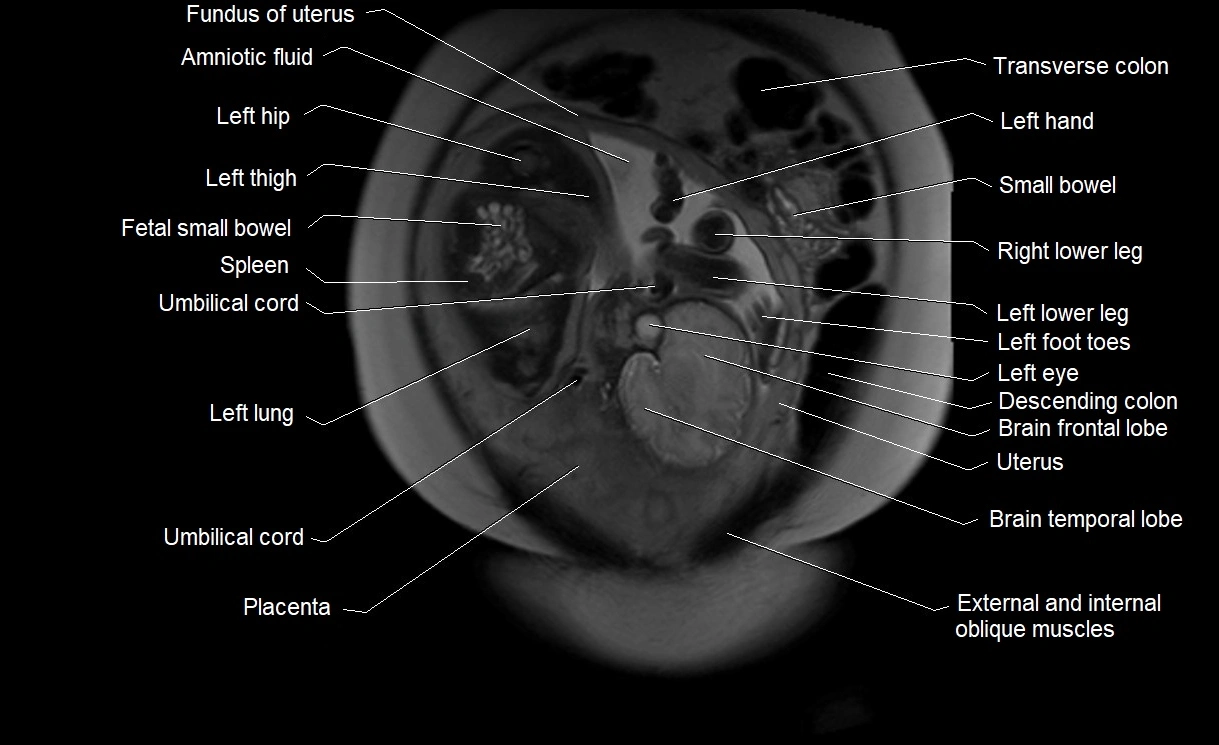

MRI Appearance

T2 HASTE (T2 GRE):

• Amniotic fluid shows very bright hyperintense signal

• Provides natural contrast against fetus and placenta

• Small particles (vernix) may appear as scattered hypointense foci within bright fluid